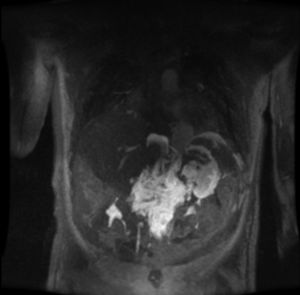

Once all the possible secondary medical etiologies potentially causing this condition had been ruled out, magnetic resonance lymphography was performed, which detected an abdominal mass with a craniocaudal diameter of 11 cm that had not been observed on the initial computed tomography scan. The lesion extended from the celiac vessels up to the renal hila surrounding the abdominal aorta in early phases (Fig. 1), with extravasation of the contrast agent into the abdominal cavity in late phases (Fig. 2).

The clinical-radiological diagnosis of bilateral chylothorax was established, in association with chylous ascites resulting from spontaneous rupture of a retroperitoneal lymphangioma.